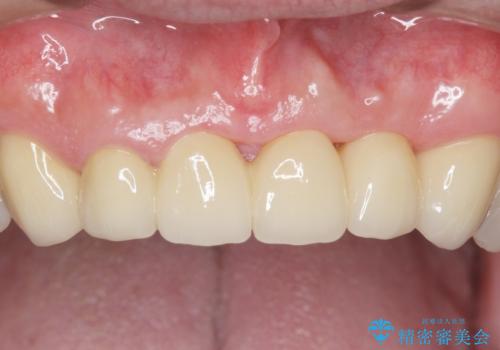

自然な仕上がりと咬み心地に大変ご満足頂けました。

「以前は出っ歯だったのにブリッジにしたことで歯並びもきれいになった!」と喜んで下さいました。

クラウンの種類:オールセラミッククラウン スタンダード